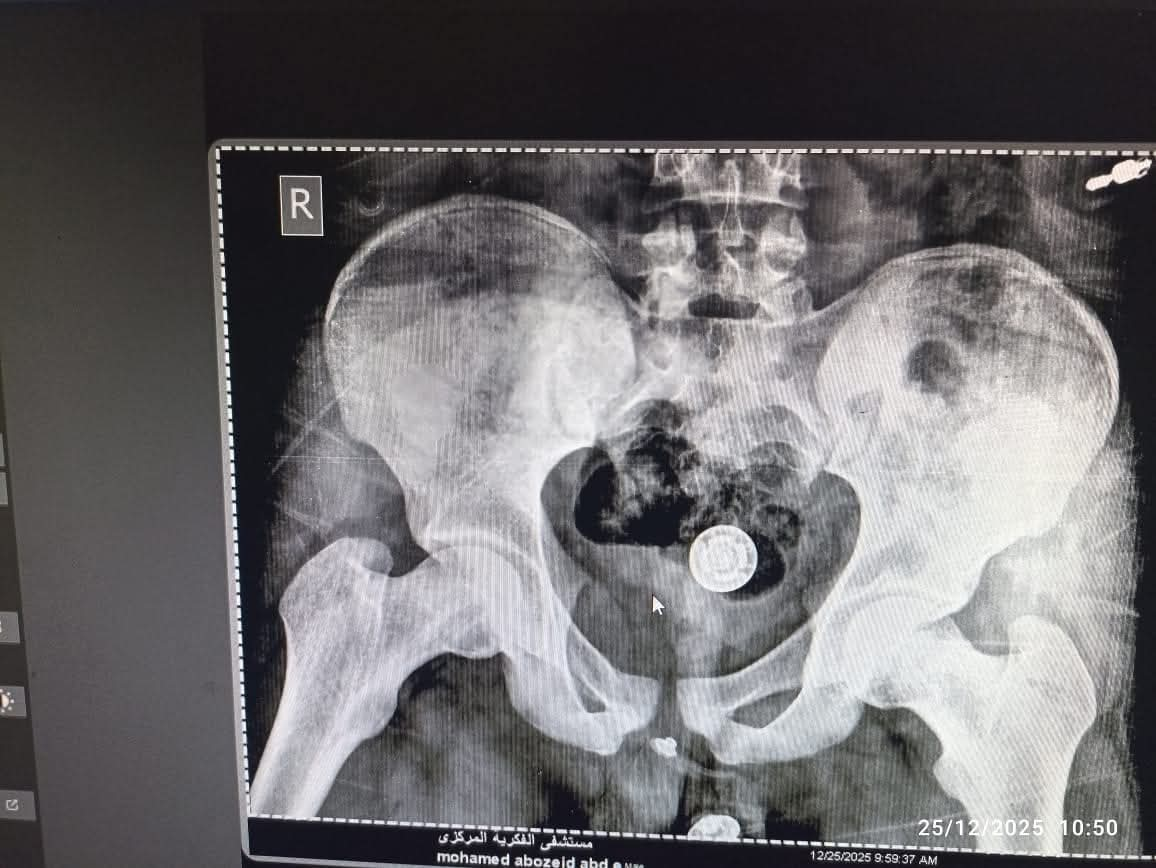

في إطار النجاحات المستمرة والجاهزية الدائمة لمستشفى الفكرية المركزي بأبوقرقاص، نجح الفريق الطبي بقسم العظام في إجراء جراحة دقيقة وعاجلة لشاب يبلغ من العمر 18 عاماً، إثر تعرضه لحادث سير أدى إلى كسر بعظمة الفخذ، حيث تم التعامل مع الحالة بكفاءة طبية عالية وتثبيت الكسر في وقت قياسي.

استقبل المستشفى شاباً في مقتبل العمر يعاني من إصابة شديدة ناتجة عن حادث سير، وبالفحص الطبي تبين وجود كسر في عظمة الفخذ، وهي من الإصابات التي تتطلب تدخلاً جراحياً دقيقاً لإعادة المصاب لممارسة حياته الطبيعية وتجنب أي مضاعفات حركية مستقبلاً.